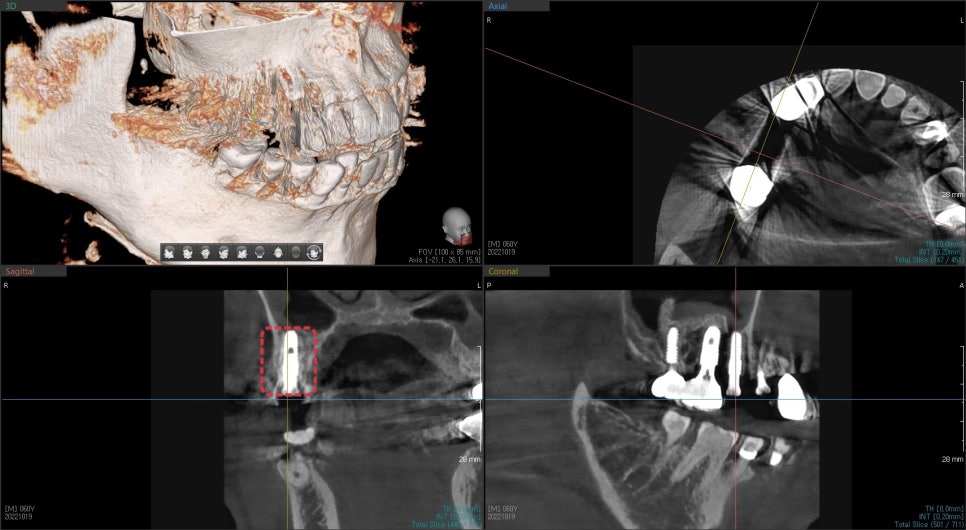

역시 초진 3D CT에서 치아를 감싸는 한쪽 벽을 이루는 뼈가 흡수되어

치아 뿌리가 노출된 상태에서 이 역시 발치 후 즉시 임플란트 식립 시

기존 잇몸을 차폐막으로 이용하여 치조골 이식술을 동반했습니다.

수술 후 4달 후 사진입니다.

임플란트 주변에 흰색 뼈가 생성된 것을 볼 수 있었습니다.

뼈와 임플란트의 고정성 평가에서도 좋은 수치를 나타내 보철치료까지 마무리했습니다.